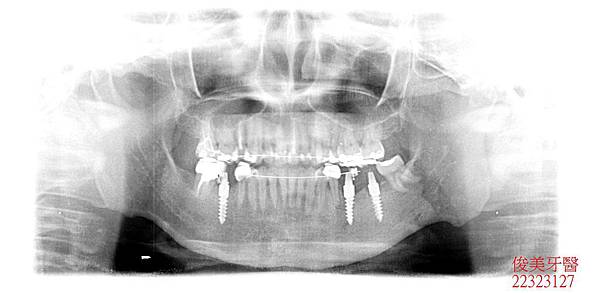

患者年約30歲,女性,於門診時表示,又蛀牙了,經醫師檢查後發現,患者因為缺牙及齒列不整

齊導致牙弓變形、咬合不佳,很多牙縫超會塞東西,且後牙未修復導致前牙牙齒有咬裂的現象,

因此建議患者考慮全口重建,將口內所有的問題分析給患者瞭解,再進行療程。

上排牙齒已有延長的現象,牙縫更容易塞東西,且沒有咀嚼功能。

蛀牙過多,且深。牙弓形狀已非標準形態。

下顎狀況 。